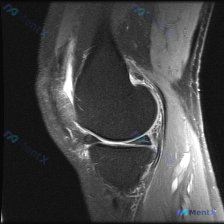

给大家分享一个很有启发的膝关节MRI读片病例,临床关注点是半月板异常,读完片发现其实核心问题不在这儿,整理一下完整分析思路。 病例影像基本信息 这是一份膝关节矢状位T2加权MRI(压脂序列),我们先整理所有客观发现: 1. 关节内结构:半月板形态完整,呈典型低信号三角表现,未见贯穿性高信号,边缘光滑...

看到一份很有启发的膝关节MRI病例,初始提示是「半月板异常」,但读片后的发现和一开始的方向完全不一样,整理一下完整分析思路跟大家分享。 一、病例影像基础信息 这是膝关节MRI矢状位T2加权图像,我们先整理所有客观发现: 1. 骨骼关节:股骨远端、胫骨近端、髌骨骨皮质完整,无明显骨折或骨质破坏,髌骨与...